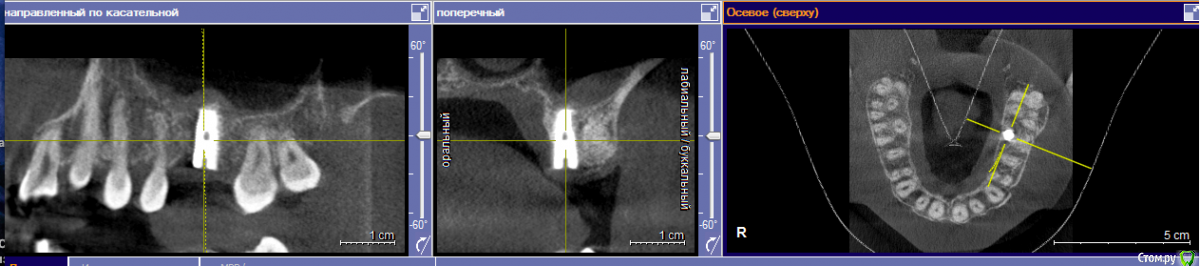

Евгений+ Опубликовано 27 июля, 2016 Поделиться Опубликовано 27 июля, 2016 Всем добрый вечер! Вчера поставил имплант, 6 сверху.Имплант смещен к небу: хирург сказал что так необходимо, т.к. зуб жевательный и нагрузка выше. Возможно ли качественное протезирование и выполнение своей функции будущим "зубом"? Ссылка на комментарий

Евгений+ Опубликовано 27 июля, 2016 Автор Поделиться Опубликовано 27 июля, 2016 (изменено) Подскажите, я правильно понимаю, что в моем случае не получится смоделировать коронку что бы центр ее оси совпадал с осью импланта? А значит, нагрузка при жевании не будет равномерно распределена вдоль оси импланта на кость. Очень настораживает наличие объема кости со стороны неба, там она вообще есть или только слизистая? Главный вопрос: оставлять или переделывать? Изменено 27 июля, 2016 пользователем Евгений+ Ссылка на комментарий